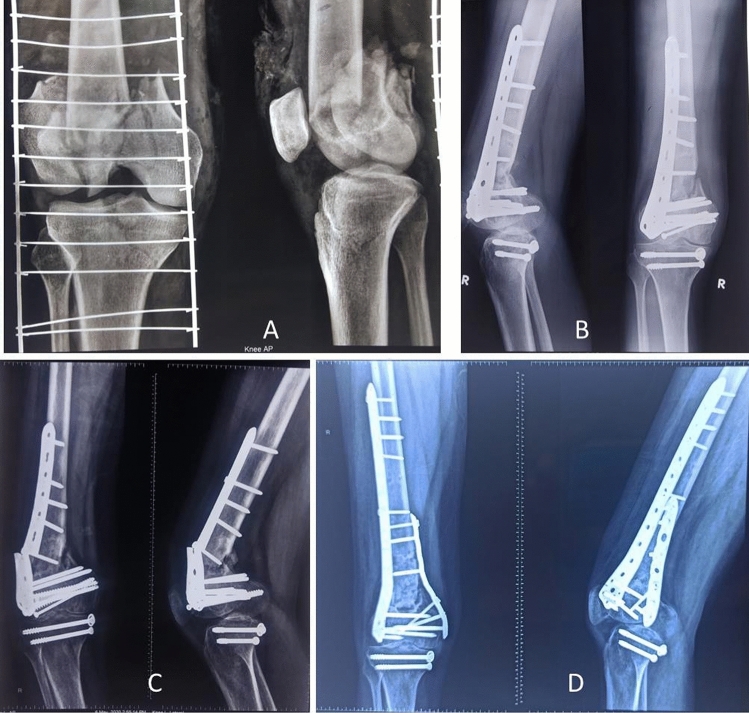

Fig. 2.

A, 41-year-male with comminuted distal femur fracture (C3); B 3 months after open reduction and internal fixation with lateral locked plate, the fracture didn't unite; C, 7 months later, he was referred to us with distal femur nonunion and broken implant; D; Four months after dual plating (lateral and medial locked plate) the fracture united, but the patient had restricted range of motion